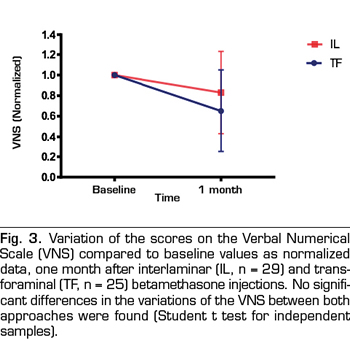

A total of 64 patients with unilateral lumbosacral radicular pain were included in the study between January, 2016 and November, 2017. Ten patients who received the treatment did not return for the follow-up (3 by parasagittal interlaminar approach, 7 by transforaminal approach). The mean age of the patients was of 51 years. Regarding sex, 32 patients were females and 8 patients were males. The mean time of pain evolution was 29 months. All the patients showed disc protrusions in spaces L4/L5 and L5/S1 with variable degrees of canal stenosis in the MRI. None of the treated patients had disc herniation. A total 29 out of 54 patients were treated with betamethasone by parasagittal interlaminar approach and 25 out of 54 patients by the transforaminal approach. Betamethasone administered by the parasagittal interlaminar approach reduced the score in the VNS by 20 %, 7.7 ± 1.5 to 6.2 ± 3,1 (statistically significant difference, p = 0,03, Student t test for paired samples) and by the transforaminal approach 36 %, of 8.3 ± 1.5 to 5.3 ± 3.3 (p = 0.0001). Figure 3 shows the normalized values of VNS (that is, showed as percentage of change) of both groups, at baseline and one month after treatment. Although the percentage of change is greater in patients in whom the transforaminal approach was used compared with the interlaminar approach, this difference is not statistically significant (p = 0.13, Student t test for independent samples).